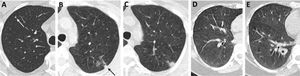

(A–F) Diffuse lung disease at baseline LDCT. Advanced destructive pulmonary emphysema (A–C) in a 65-year-old man from NLST who died of respiratory disease (ICD code J449) 835 days after randomization. Interstitial lung disease (D–F) in a 73-year-old man from NLST who died of respiratory disease (ICD code J849 – interstitial pulmonary disease unspecified) 2462 days after randomization.